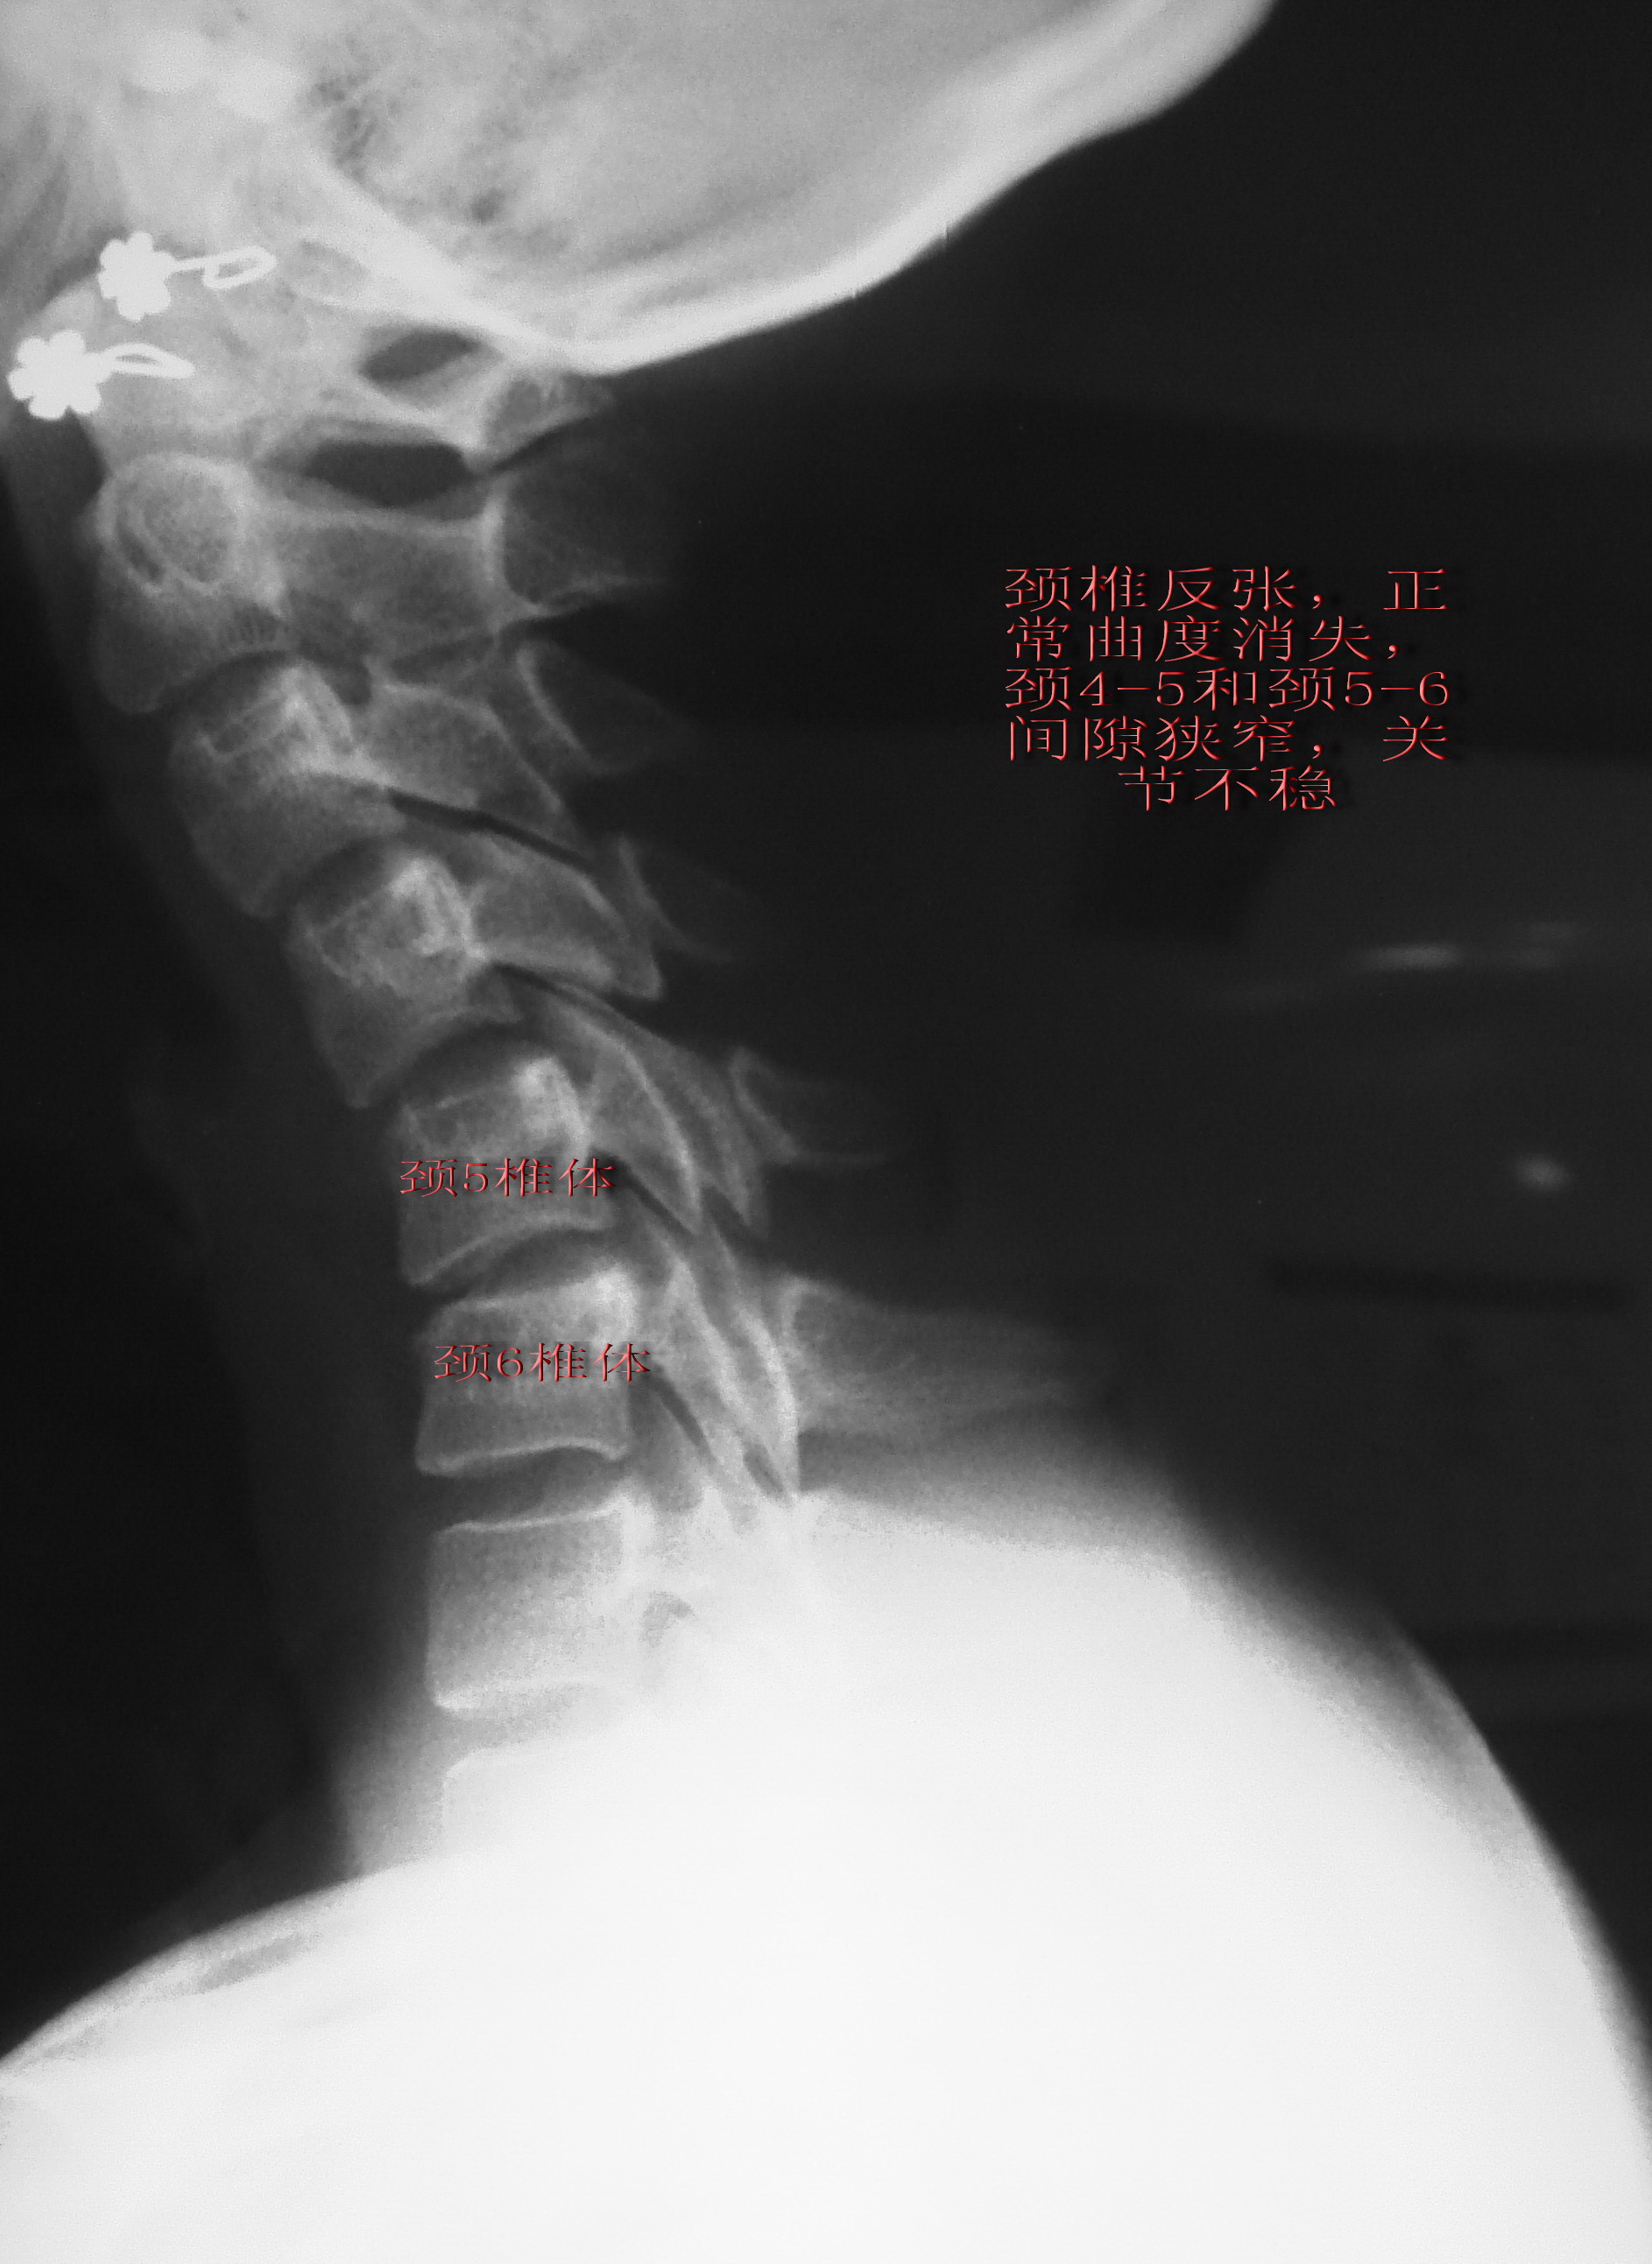

颈椎病前路手术-椎间盘切除cage内固定 - 好大夫在线

颈椎病的微创治疗